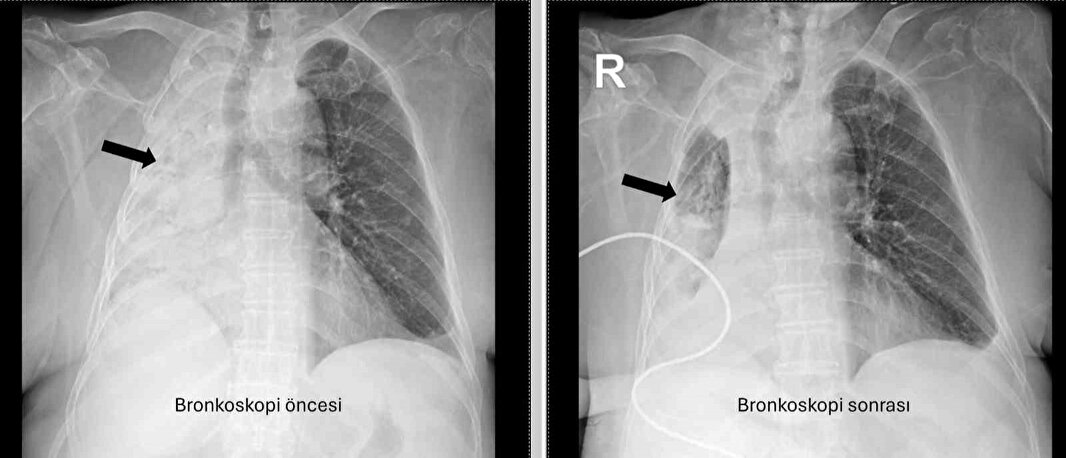

PAÜ Hastaneleri Göğüs Hastalıkları Anabilim Dalı Öğr. Üyesi Prof. Dr. Göksel Altınışık Ergur, tarafından yapılan tetkiklerde sağ akciğere giden hava yolunun bütünüyle kapalı olduğu görüldü.

"Fleksibl (esnek, eğilip bükülebilir) bronkoskop ile hava yolları incelenirken çok yoğun ve koyu sekresyon olduğu, bunun iyice temizlenmesi sonucunda ancak hava yollarının incelenebileceği görüldü. Aspiratör (içerideki salgıları emmeye yarayan bir cihaz) sayesinde hava yollarına steril sıvı verilip emilerek bu temizlik yapıldı. Sonrasında sağ akciğere giden hava yolunda sarı bir nesne olduğu görüldü. Bu hâliyle yabancı cisim olduğu anlaşıldığı gibi bunun mısır tanesine benzerliği de açıktı. Yabancı cismi çıkarma işlemi genel anestezi altında, rijit bronkoskop ile yapılmak üzere planlanabilirdi; çünkü bu durumun tedavisi yabancı cismin oradan, ek sorun oluşturmaksızın çıkarmaktı. Ancak, genel anestezi altındaki bir işlem için hastanın genel durumu bozuk olduğundan, özellikle ek hastalıkları ve enfeksiyon varlığı ile işlem riski artacağından hastadaki cismin fark edildiği sırada çıkarılmasına şans vermek daha uygun görüldü.

Hava yolu içindeki sıvıları emen aspiratörün gücünü kullanılarak cismin çıkarılması mümkündü. Bronkoskobun ucu, sarı cismin gövdesine dayanıp aspiratör ile emme sayesinde ikisi birbirine sımsıkı yapıştırıldı. Emme gücünün azaltılmamasına dikkat ederek yabancı cisim ve bronkoskop, aynı zamanda hava yollarından dışarıya başarı ile çıkarıldı. İşlem sonrasında hasta yakınına mısır tanesi açısından tıbbi öykü yeniden sorulduğunda, hastamızın bundan beş ay önce yediği pizzanın üzerinde mısır taneleri olduğu öğrenildi. O sırada ani bir yakınma ortaya çıkmadığı için böyle bir ihtimal akla gelmemişti. Düşkün hastalar taneli gıdalar yerken, bu durumun fark edilmeden de gelişebileceğini göstermesi açısından önemli olan bu tablo, hastaların bir dedektif titizliği ile değerlendirilmesi gerekliliğini bir kez daha ortaya koymaktadır"